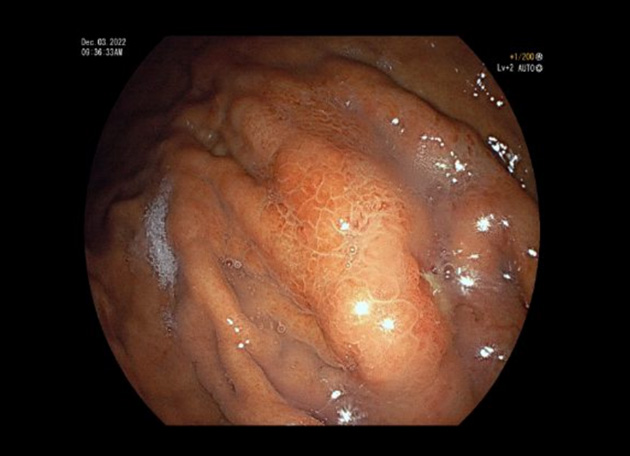

위암도 초기에는 대부분 아무런 증상이 없는 경우가 많으며, 정기적인 위내시경 도중 우연히 발견되는 경우가 많고, 진행된 위암의 경우, 오심, 구토, 소화불량 등의 증상이 나타날 수 있습니다. 정기적인 위내시경 검사를 통해 위를 직접 관찰하고 필요시 조직 검사를 통해 위암이 의심되는 부위를 확인함으로써 위암을 조기에 발견할 수 있습니다.